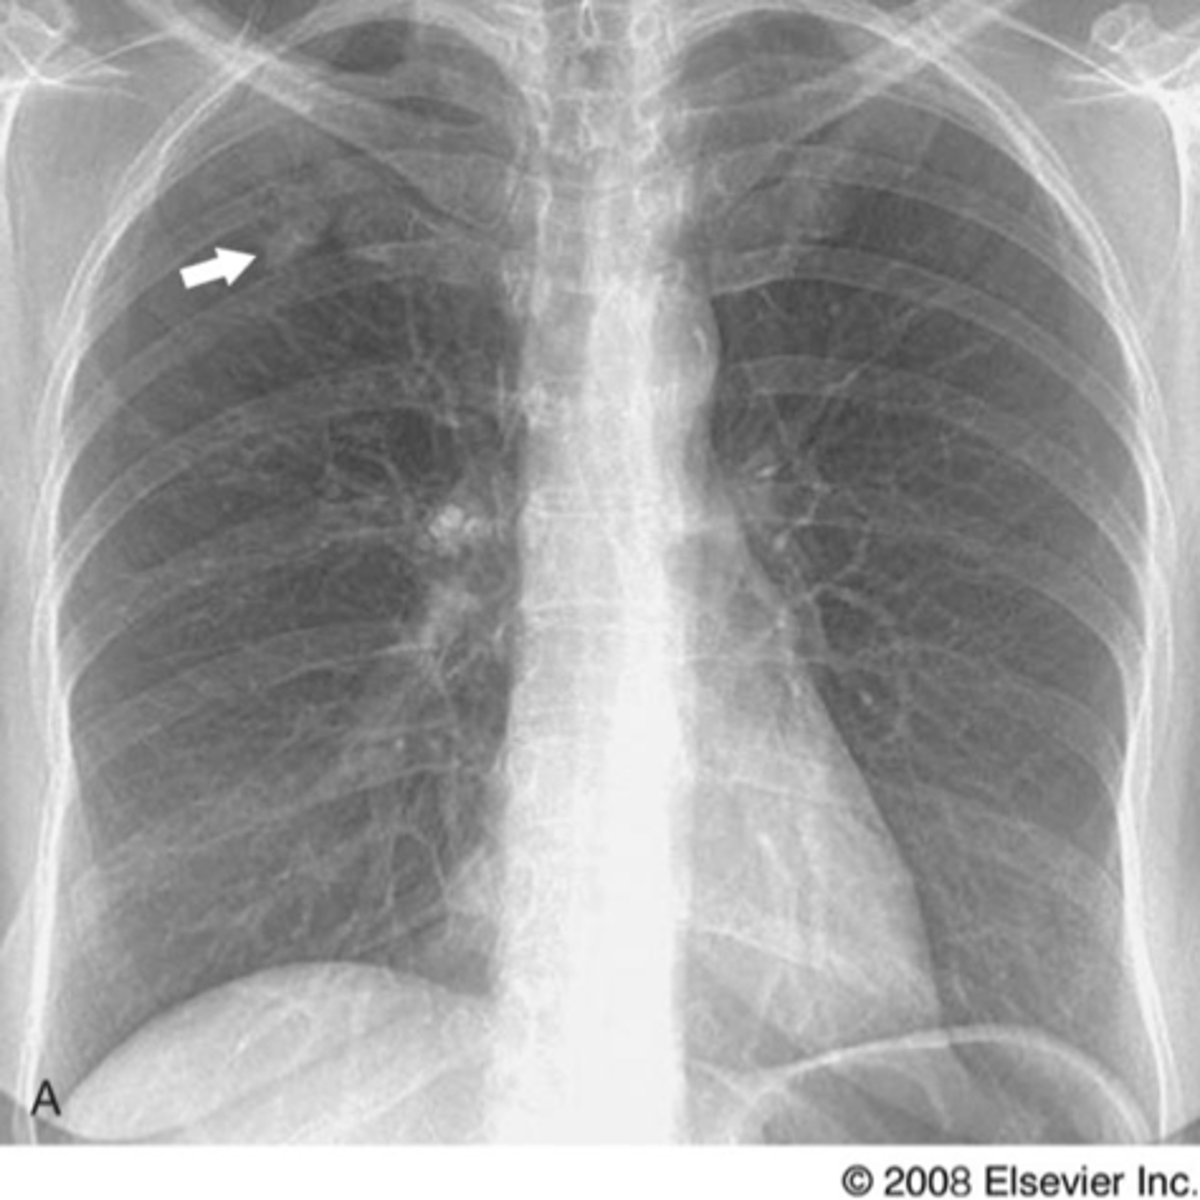

Solitary pulmonary nodule

Nodule